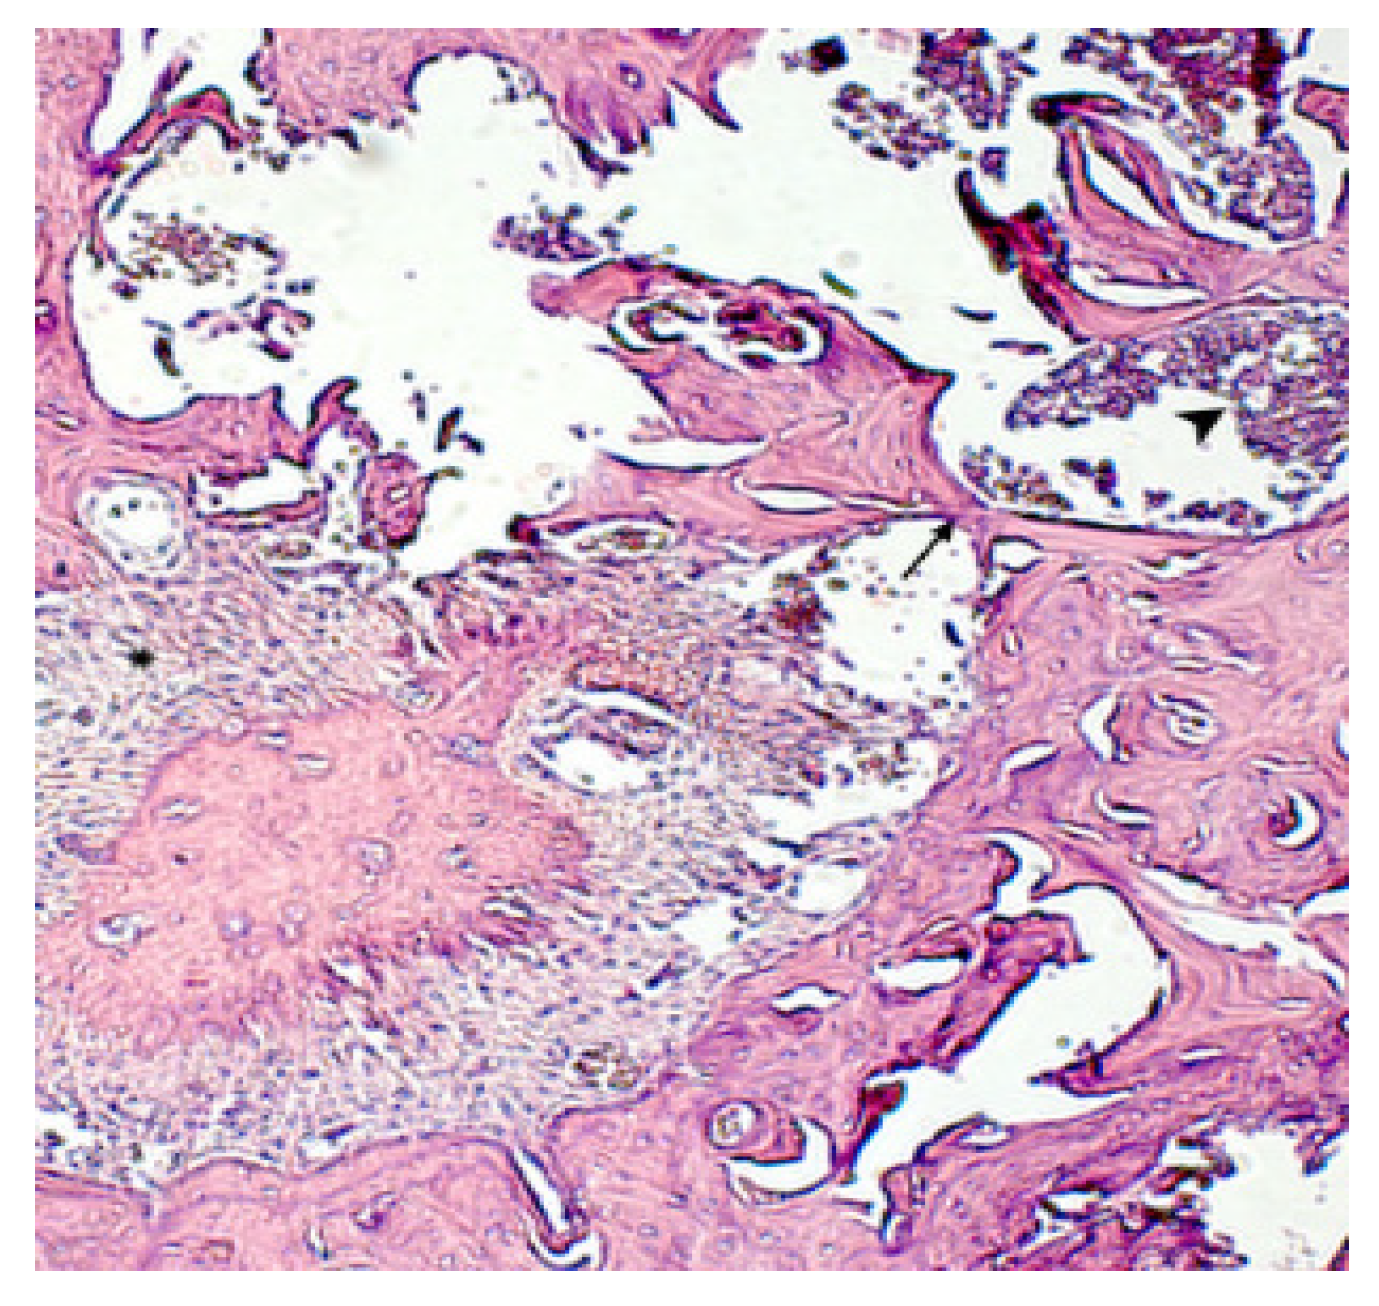

) are recorded. Hematoxylin-eosin staining. Magnification x250.

). Hematoxylin-eosin staining. Magnification x400.

) are detected, in the bone tissue “isolated” osteocytes (^). Hematoxylin-eosin staining. Magnification x480.